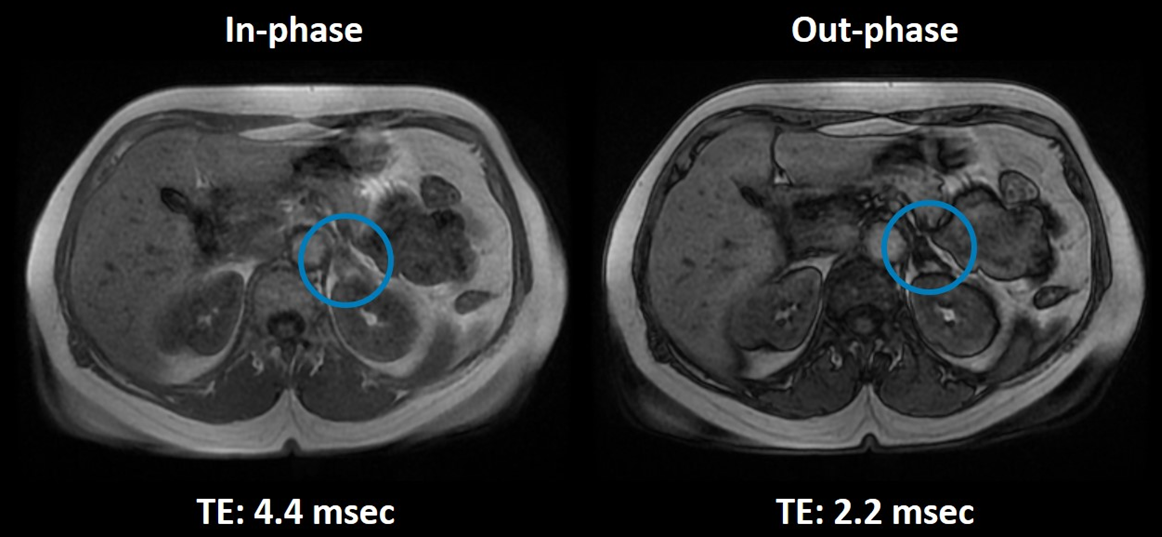

Χρήση του τεχνικού σφάλματος χημικής μετατόπισης δεύτερης τάξης για την διαφορική διάγνωση καλοήθους ή κακοήθους εξεργασίας στο αριστερό επινεφρίδιο (μπλε κύκλος). Η βλάβη παρουσιάζει απώλεια σήματος στην εικόνα εκτός φάσης (δεξιά), χαρακτηριστικό το οποίο την κατατάσσει ως ένα καλοήθες αδένωμα του αριστερού επινεφριδίου.

Το σφάλμα χημικής μετατόπισης δεύτερης τάξης, μπορεί να γίνει εμφανές στις εικόνες σαν σκοτεινοί δακτύλιοι στα όρια των ιστών που περιέχουν νερό και λίπος. Λόγω αυτής της εμφάνισης το σφάλμα είναι γνωστό και σαν black boundary. Αμέσως μετά από τη διέγερση με παλμό ΡΣ, οι εγκάρσιες μαγνητίσεις των πρωτονίων είναι συμφασικές. Στις SE ακολουθίες, λόγω χρήσης παλμού ΡΣ 180° για την επανεστίαση  του σήματος, τα πρωτόνια του λίπους και του νερού είναι συμφασικά κατά την διαδικασία της ανάγνωσης. Στις GRE ακολουθίες, όμως, τα πρωτόνια νερού και λίπους θα βρίσκονται εντός και εκτός φάσης περιοδικά, εξαιτίας της διαφοράς στις μεταπτωτικές τους συχνότητες, η οποία δεν διορθώνεται από την επανεστίαση με πηνία βαθμίδας. Για παράδειγμα, όταν χρησιμοποιείται ακολουθία GRE σε μαγνητικό πεδίο έντασης 1.5 Τ με χημική μετατόπιση 220 Hz, η εναλλαγή των πρωτονίων από συμφασικά σε εκτός φάσης (και το αντίστροφο) συμβαίνει περίπου κάθε 2.2 msec. Επομένως, σε χρόνους ΤΕ ≈ 4.4msec, 8.8msec κ.ο.κ τα πρωτόνια θα είναι συμφασικά, ενώ σε χρόνους ΤΕ ≈ 2.2msec, 6.6msec κ.ο.κ τα πρωτόνια θα είναι εκτός φάσης. Τα voxels που περιλαμβάνουν σχετικά ίδιο αριθμό πρωτονίων νερού και λίπους σε χρόνους εκτός φάσης θα αναδεικνύονται με απώλεια σήματος. Το συγκεκριμένο τεχνικό σφάλμα είναι εμφανές τόσο στον άξονα της φάσης όσο και στον άξονα της συχνότητας καθώς είναι ανεξάρτητο της χωρικής κωδικοποίησης.

Σημείωση: Το τεχνικό σφάλμα χημικής μετατόπισης δεύτερης τάξης χρησιμοποιείται εποικοδομητικά για τον χαρακτηρισμό των ιστών σε περιπτώσεις όπως είναι η διάγνωση αδενώματος του επινεφριδίου (εικόνα), η ανάδειξη λιπώδους διήθησης του ήπατος, η ανίχνευση οστικών μεταστάσεων και η διαφορική διάγνωση καλοήθους ή κακοήθους εξεργασίας στον θύμο αδένα. Ο χαρακτηρισμός των ιστών γίνεται συγκρίνοντας την ένταση του σήματος στις εικόνες in-phase με τις εικόνες out-of-phase. Ιστοί που χάνουν το σήμα τους στις εικόνες out-of-phase θεωρούνται καλοήθεις αφού περιέχουν λίπος.